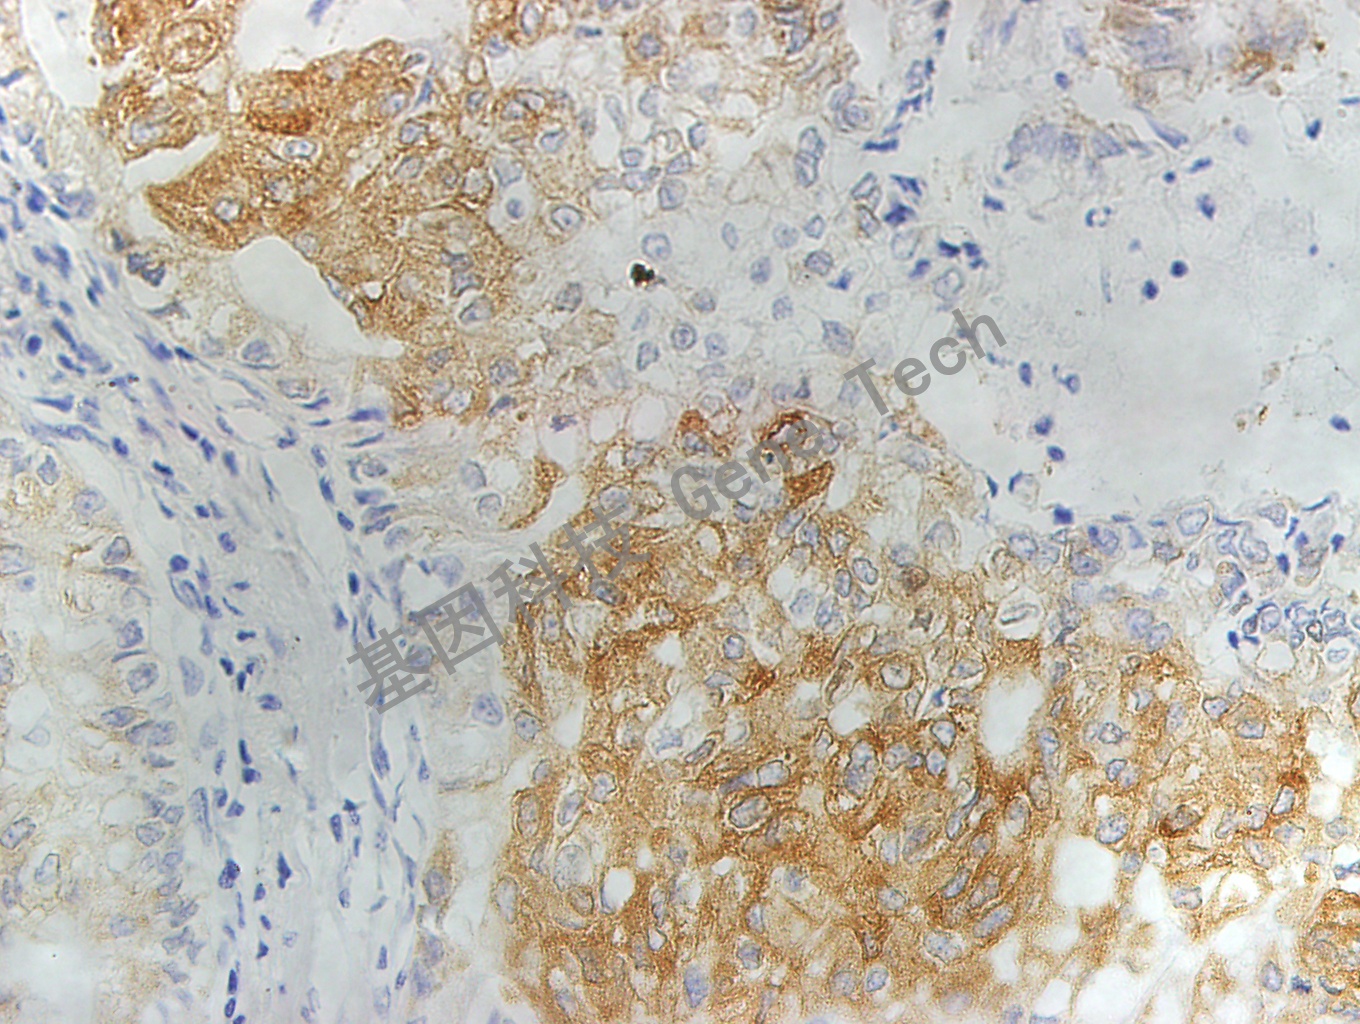

| 预处理:高pH热修复 | 阳性部位:细胞浆 | 阳性对照:乳腺癌 |

| 肺石蜡切片,用 MRP1(GT2015)染色,细胞浆阳性,DAB 显色 | ||